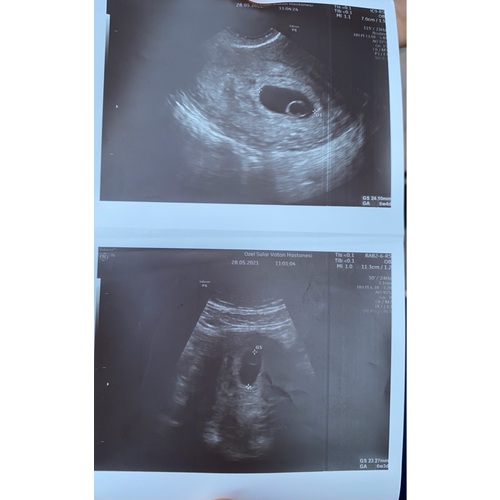

Vruchtzakje 6 Weken Miskraam. Hoe Lang Blijft Een Leeg Vruchtzakje Zitten Bij Een Miskraam? Ik ben afgelopen maandag voor nog een controle geweest (ruim een week na de miskraam) en toen was het vruchtzakje verdwenen Kreeg toen ook de boodschap: of buitenbaarmoederlijke zwangerschap, of wordt een miskraam, of je bent nog niet zo ver

Een miskraam bij 5 of 6 weken kan op verschillende manieren verlopen Nadat de miskraam volledig tot stand is gekomen of de curettage succesvol is uitgevoerd is de zwangerschap beëindigd en.

Een miskraam bij 5 of 6 weken kan op verschillende manieren verlopen Kreeg toen ook de boodschap: of buitenbaarmoederlijke zwangerschap, of wordt een miskraam, of je bent nog niet zo ver 'Ik wist niet hoe een miskraam bij zes weken eruit ziet' Een miskraam na 6 weken

6 weken zwanger Ontdek je symptomen en to do's. Sommige vrouwen merken er weinig van, terwijl het bij andere verloopt als een heftige menstruatie. Ik had 3 dagen na mijn gemiste menstruatie getest en mijn positieve streepje was bijna niet te zien, zo licht! Daarna een clear blue test gedaan en die gaf aan 1/2 weken zwanger